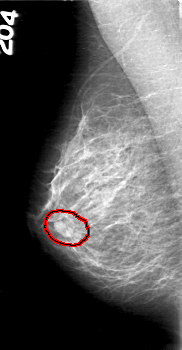

D_4029_1.RIGHT_MLO

FILE: D_4029_1.RIGHT_MLO.OVERLAY

TOTAL_ABNORMALITIES 1

ABNORMALITY 1

LESION_TYPE MASS SHAPE OVAL MARGINS OBSCURED

ASSESSMENT 0

SUBTLETY 4

PATHOLOGY BENIGN

TOTAL_OUTLINES 1

BOUNDARY